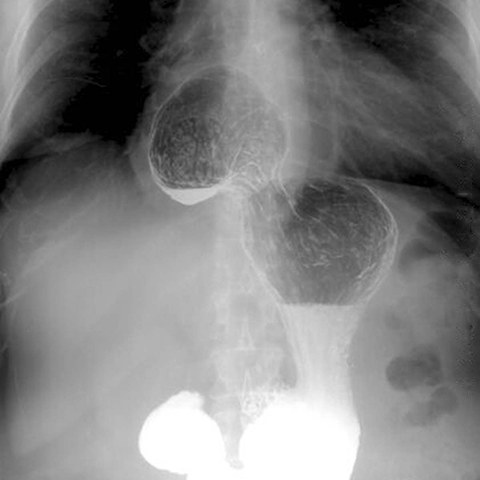

Upper barium GI series, Paraesophageal Hernia [1 of 2]